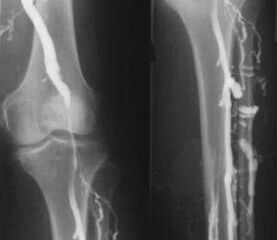

The most common instrumental diagnostic method is the use of ultrasound examination of leg venous vessels.This technique allows you to visualize the vascular system and identify the degree of progress of the pathological process.

- Phlebo.

- Photoplethysmography.

The use of venous occlusion plethysmography makes it possible to determine the amount of blood in the lower leg veins.